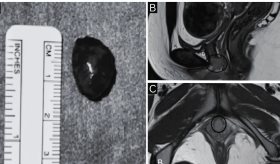

La Fundación Cardioinfantil – LaCardio realizó el pasado 14 de mayo la primera ablación biliar por radiofrecuencia bipolar en el país, utilizando el dispositivo especializado Habib EndoHPB Bipolar Radiofrequency Catheter.

El paciente de 63 años fue diagnosticado con un tumor biliar avanzado, colangiocarcinoma, ha sido el primer paciente que ha recibido este procedimiento en Colombia, llevado a cabo mediante cirugía por un equipo multidisciplinario que integró expertos en cirugía hepática, radiología intervencionista, anestesiología y gastroenterología.

El objetivo principal fue reducir el volumen tumoral y mejorar la calidad de vida del paciente, permitiendo el drenaje adecuado de la vía biliar obstruida.

"Utilizamos un dispositivo que es el Habib EndoHPB Bipolar Radiofrequency Catheter que lo que permite es hacer una necrosis del tumor, es un catéter de ablación que actúa con calor, y lo que hace es obstruir el drenaje biliar mediante este catéter lo que nosotros hacemos es quemar el tumor.

De esta forma, se abre un túnel en la obstrucción, para que el drenaje biliar continúe como de costumbre, esto les da mejor calidad de vida, y aunque probablemente no se pueda desaparecer el tumor, ya que esta intervención se hace de manera paliativa, en pacientes que ya han sido sometidos a unos tratamientos convencionales.

"Logramos impermeabilizar el ducto biliar de este paciente, ya le habíamos hecho intervenciones previas y el tumor estaba creciendo y estaba generando obstrucción del drenaje biliar, y con con los resultados obtenidos con la ablación, logramos abrir un espacio a ese drenaje normal que debe tener el ducto biliar y mejorar drenaje hepático." explicó.